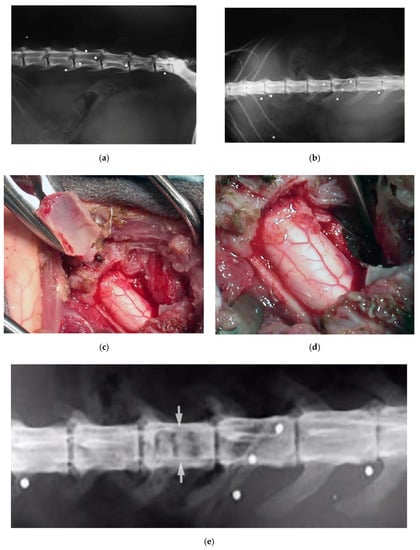

Dog, female, four years old, 0.8 kg, paraplegic, diagnosed with a T13-L1 fracture-luxation with hyperkyphosis secondary to a road accident. The dog underwent a thoracic laminectomy with a monolateral vertebral stabilization T13-L1 with plate and screws (Figure 5). By the six-month follow-up, the dog had partially recovered.

Figure 5.

X-ray showing a T13-L1 fracture with hyperkyphosis in a paraplegic dog (a). A safe thoracic piezoelectric laminectomy was obtained with an angled sharp tip (OT2, Osteotomy Tips Kit, Mectron Medical Technology, Genoa, Italy) piezoelectric bone scalpel (b). Dorsal monolateral vertebral stabilization T13-L1 with plate and screws. Noteworthy, piezoelectric scalpel with a different straight tip was used as tapper for the screws placement (c).